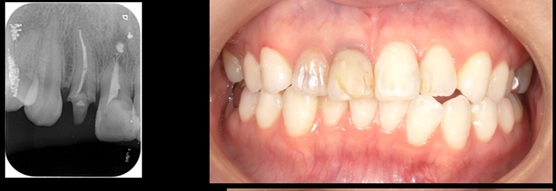

CTG(結合組織移植術)歯肉を移植する

治療前

治療後

施術名 | CTG(結合組織移植術)をしてジルコニアボンド |

主訴 | 前歯の破折 |

施術の副作用(リスク) | 感染 |

施術の価格 | 66,000円 |

コメント | 50代男性。前歯が破折したためインプラント埋入だけでは審美が著しく劣ると判断したため骨も吸収していたため骨も作り(GBR)、CTG(結合組織移植術)もしました。 |